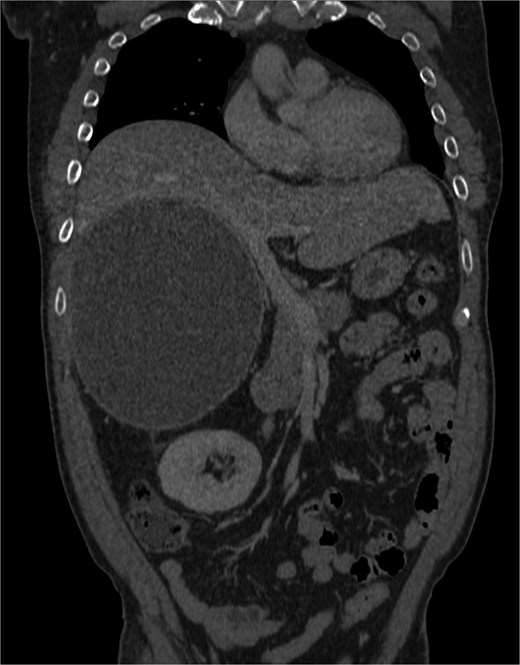

Positron-emission tomography (PET) scan with F18-Fluorodeoxy-glucose (FDG) and C11-Acetate, and combined contrast-enhanced computerized tomography (CT) revealed a predominantly cystic mass measuring ~14.8 × 17.9 × 18.6 cm located on the right side of the abdomen, arising from the retroperitoneal space with close approximation to the adrenal gland. It displaced the adjacent organs, including pancreas and the right kidney; A tiny mural calcification and focal hypermetabolic activity within the cyst wall raised the possibility of malignant transformation (Figs 1–4).

Cystic mass with mural calcification and tissue components in the posteroinferior portion, closely abutting the right kidney and adrenal.